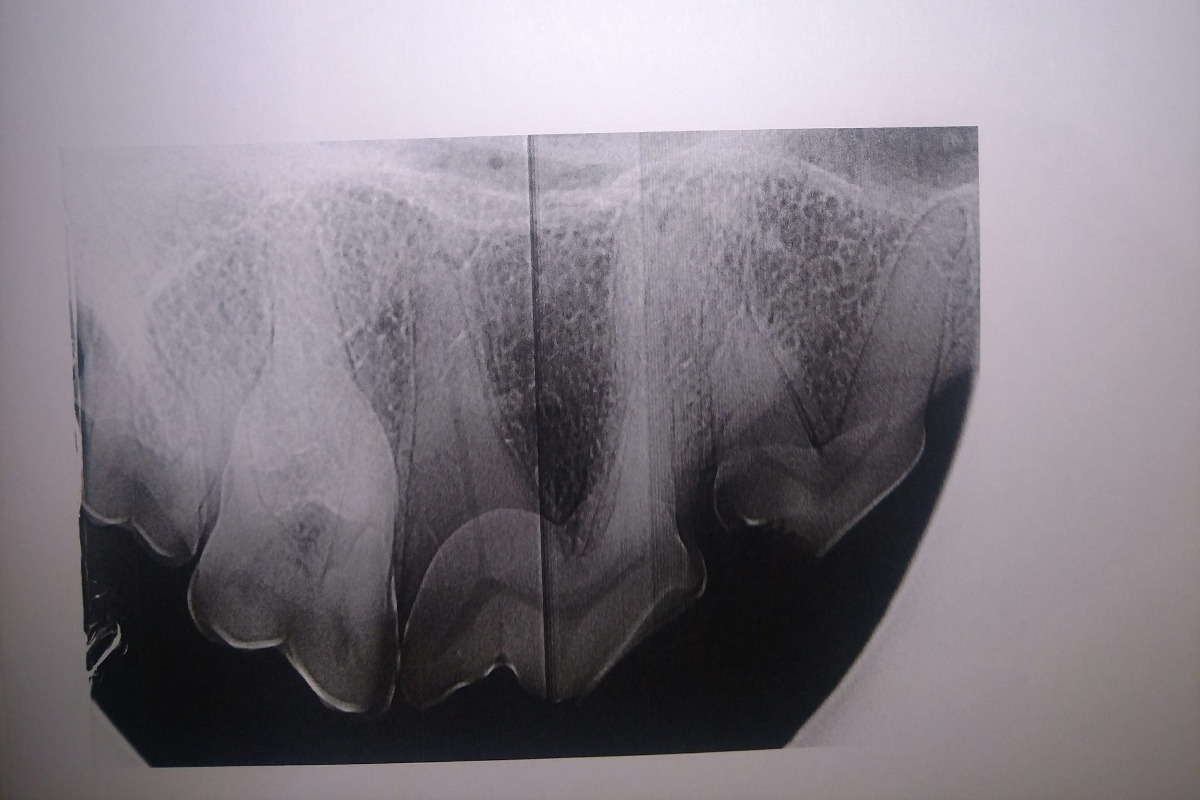

The radiographs laid out a dim story of that long term damage: all 4 canine teeth were dead, 2 of those canines were broken off from the recent attempt on the gate; all of her lower incisors, and several molars on each side were also dead. The vet was surprised, in spite of massively evident wear and tear, that her upper incisors appeared to still be alive. More of her teeth were dead than live. However, there was some good news in that her gums were completely free of gum disease, she had very little plaque and tartar buildup, and that she hadn't lost any of the bone her teeth were seated in.

AFTER PHOTOS: (left upper and lower canine root canals, cleaning)

The following photos are her radiographs for anyone that knows how to read them, so you can see all the dead teeth that need future extractions, and some show the root canals: